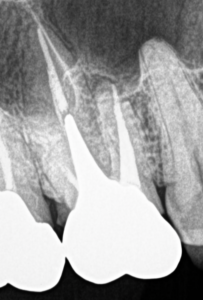

そして最後にケースを提示した。